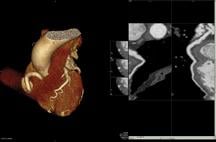

The CVDC acquired the Toshiba Aquilion ONE dynamic volume CT system to perform advanced cardiovascular CT imaging. Dr. Albert uses the Aquilion ONE for imaging of the coronary arteries because of the high image resolution of the system.

The Aquilion ONE utilizes 320 ultra-high resolution detector rows (0.5 mm in width) to image the heart in a single gantry rotation. The unparalleled result produces a 4D clinical video showing up to 16 cm of anatomical coverage, enough to capture the entire heart, and show its movement such as blood flow. The ability to image the heart in a single rotation significantly reduces radiation dose as it limits exam time and eliminates multiple exposures to radiation.

“CT is the gold standard for coronary imaging because of the high-quality image resolution and fast acquisition time,” stated Dr. Albert. “The rapid, efficient cardiac imaging and the lower radiation dose of the Aquilion ONE CT system are the perfect fit for the new cardiovascular center. The Aquilion ONE is able to lower radiation dosage by up to 80 percent, making CT imaging safer for patients.”